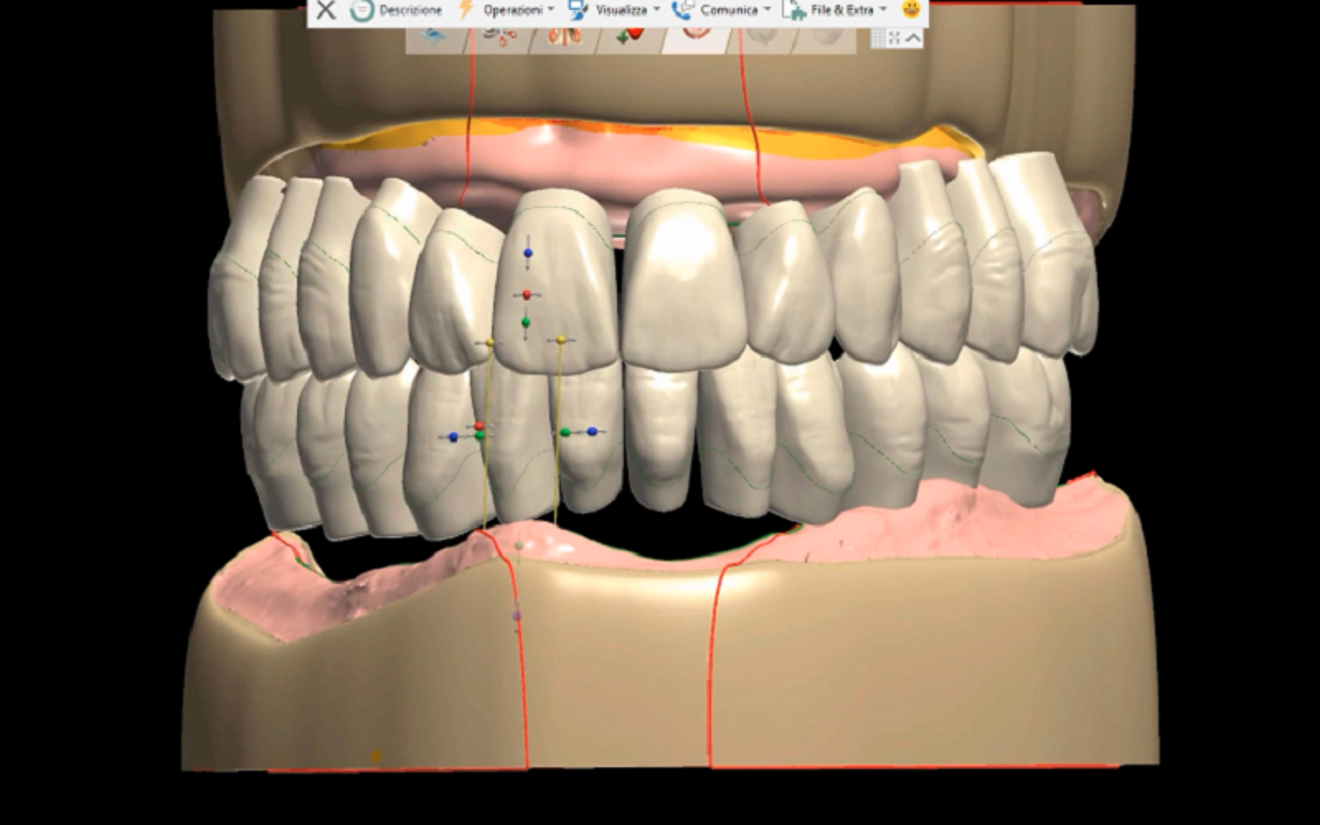

The 3D files of the prostheses were exported to the Ivotion denture system’s specific CAM module (Ivoclar; Figs. 4–6). The prostheses were milled using the Ivoclar-exclusive Shell Geometry processing capability of the R5 (Figs. 7–9). In 4 hours, the complete maxillary and mandibular prostheses had been fabricated (Fig. 10). For the maxillary prosthesis, we immediately relined it after removing the framework that had been screwed to the prosthesis and then screwed it in (Fig. 11). Re-evaluation with a digital facebow and data comparison were made possible by remote control (Figs. 12 & 13).

Fig. 6: Maxillary and mandibular prostheses designed with Ivotion libraries.